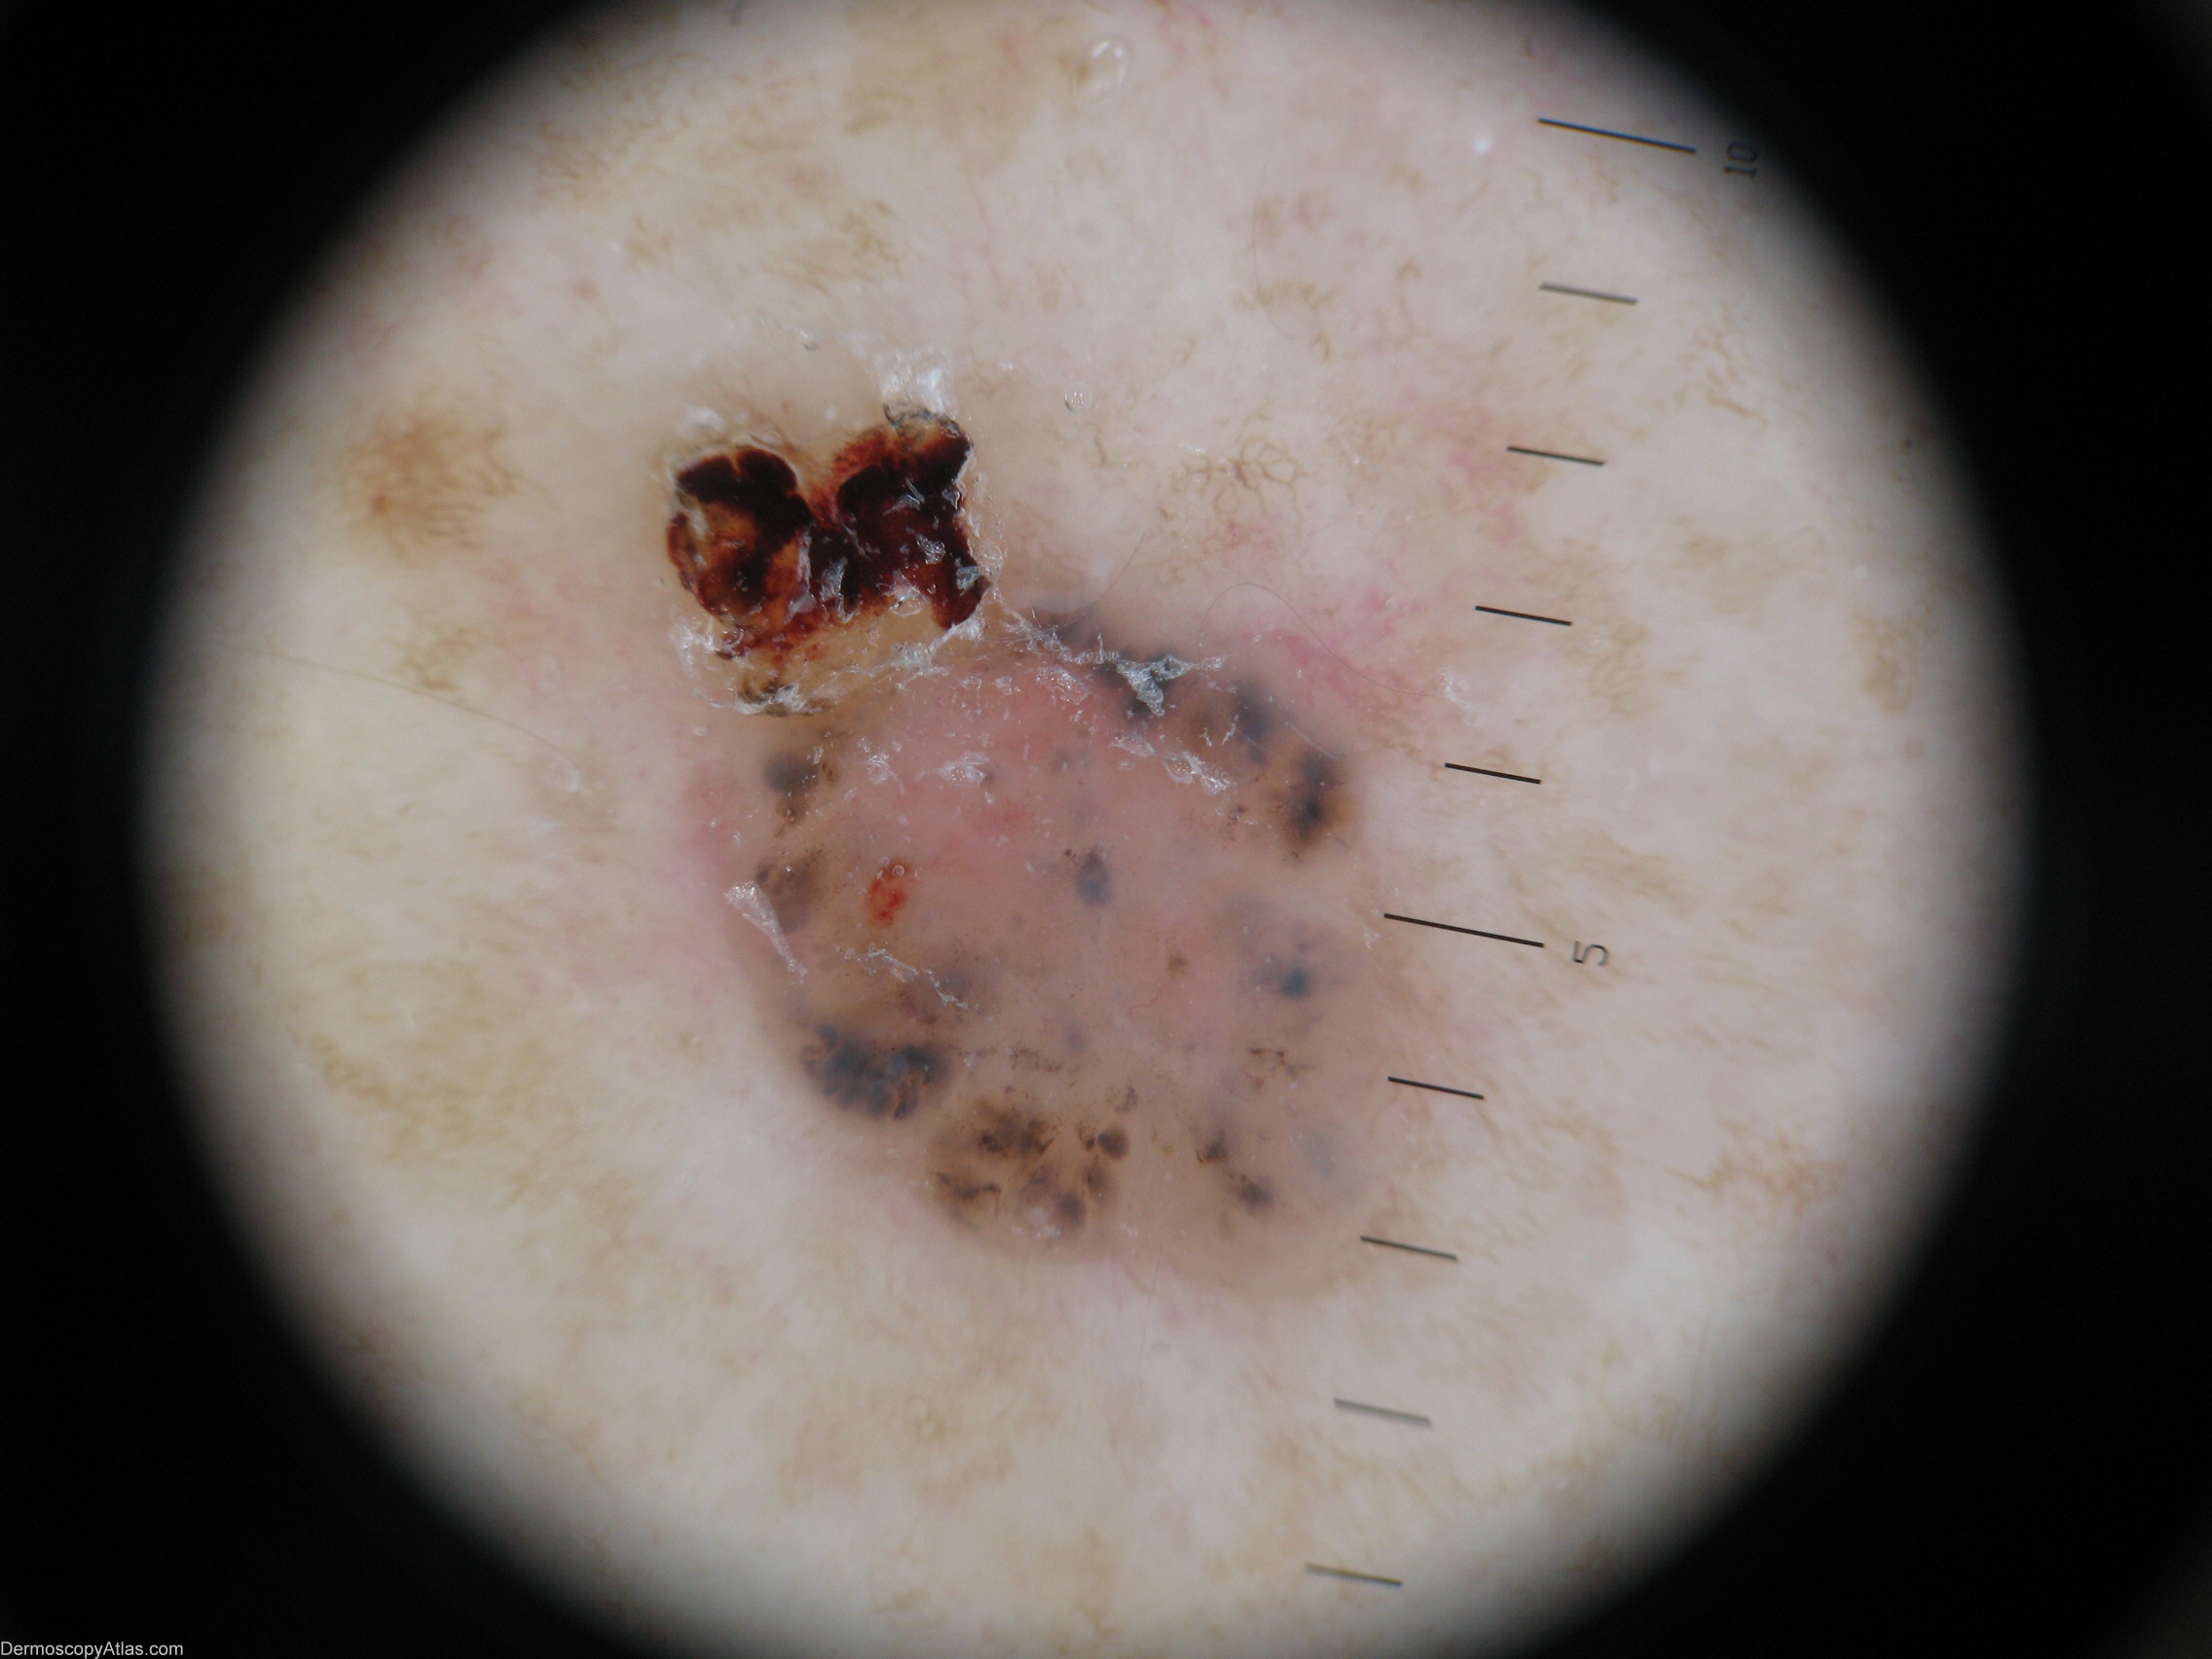

Image Number #3039 (BCC pigmented)

Site: Back

Diagnosis: BCC pigmented

Description: Macro view

This elderly lady was unaware of this lesion on her back.

It shows classical features of a pigmented BCC with Blue ovoid nests/Blue clods.

It has few vessels but has a dishwater colour often seen in a BCC.  It has some ulceration.

A good example of a Maple leaf like structure is seen at 7 o'clock.